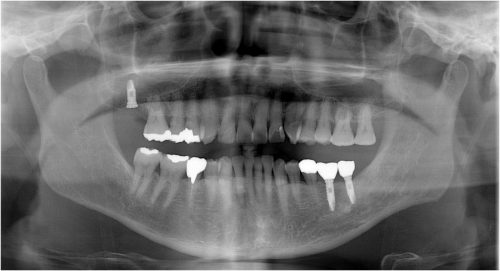

インプラント 右上4567 川口で精密インプラントなら さかえ歯科

2017年02月2日